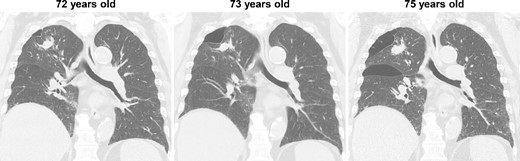

During the computed tomography (CT) scan of the 62-year-old patient, physicians did not point out infiltrating shadows in the right upper lobe caused by suspected pulmonary tuberculosis. Therefore, a chest CT scan was not performed until the patient developed a right pneumothorax at age 70. At 70 years old, the patient developed pneumothorax in his right lung; a CT scan revealed a 3.2 cm mass with satellite lesions in the right upper lobe, as well as pulmonary cysts on the peripheral side of the mass (Fig. 1). At this point, a retrospective review of the patient’s earlier CT images (at age 62 years) confirmed that there were some shadows indicative of pulmonary infiltration in the upper lobe of the right lung, although pulmonary cysts were not visible. The pulmonary cysts were considered to have caused the patient’s pneumothorax, which resolved following chest drainage. A bronchoscopy was performed after the pneumothorax improved, with brushing cytology and bronchoalveolar lavage cytology revealing no malignant cells. An acid-fast bacilli culture of the patient’s bronchoalveolar lavage fluid and the T-cell spot test for tuberculosis infection (T-SPOT.TB) were both negative. An 18F-fluorodeoxyglucose positron emission tomography/CT scan showed a maximum standard uptake value (SUVmax) of 1.8 in the lung mass. Since the lung mass was not suspected to be aggressively malignant [8], careful follow-up was performed, involving another CT scan. The lung mass was not enlarged; however, some growth of the pulmonary cysts was observed (Fig. 2).

CT images of the intervening period between the initial and relapsed pneumothorax; no enlargement of the lung mass was observed, but gradual enlargement of the pulmonary cysts was apparent.